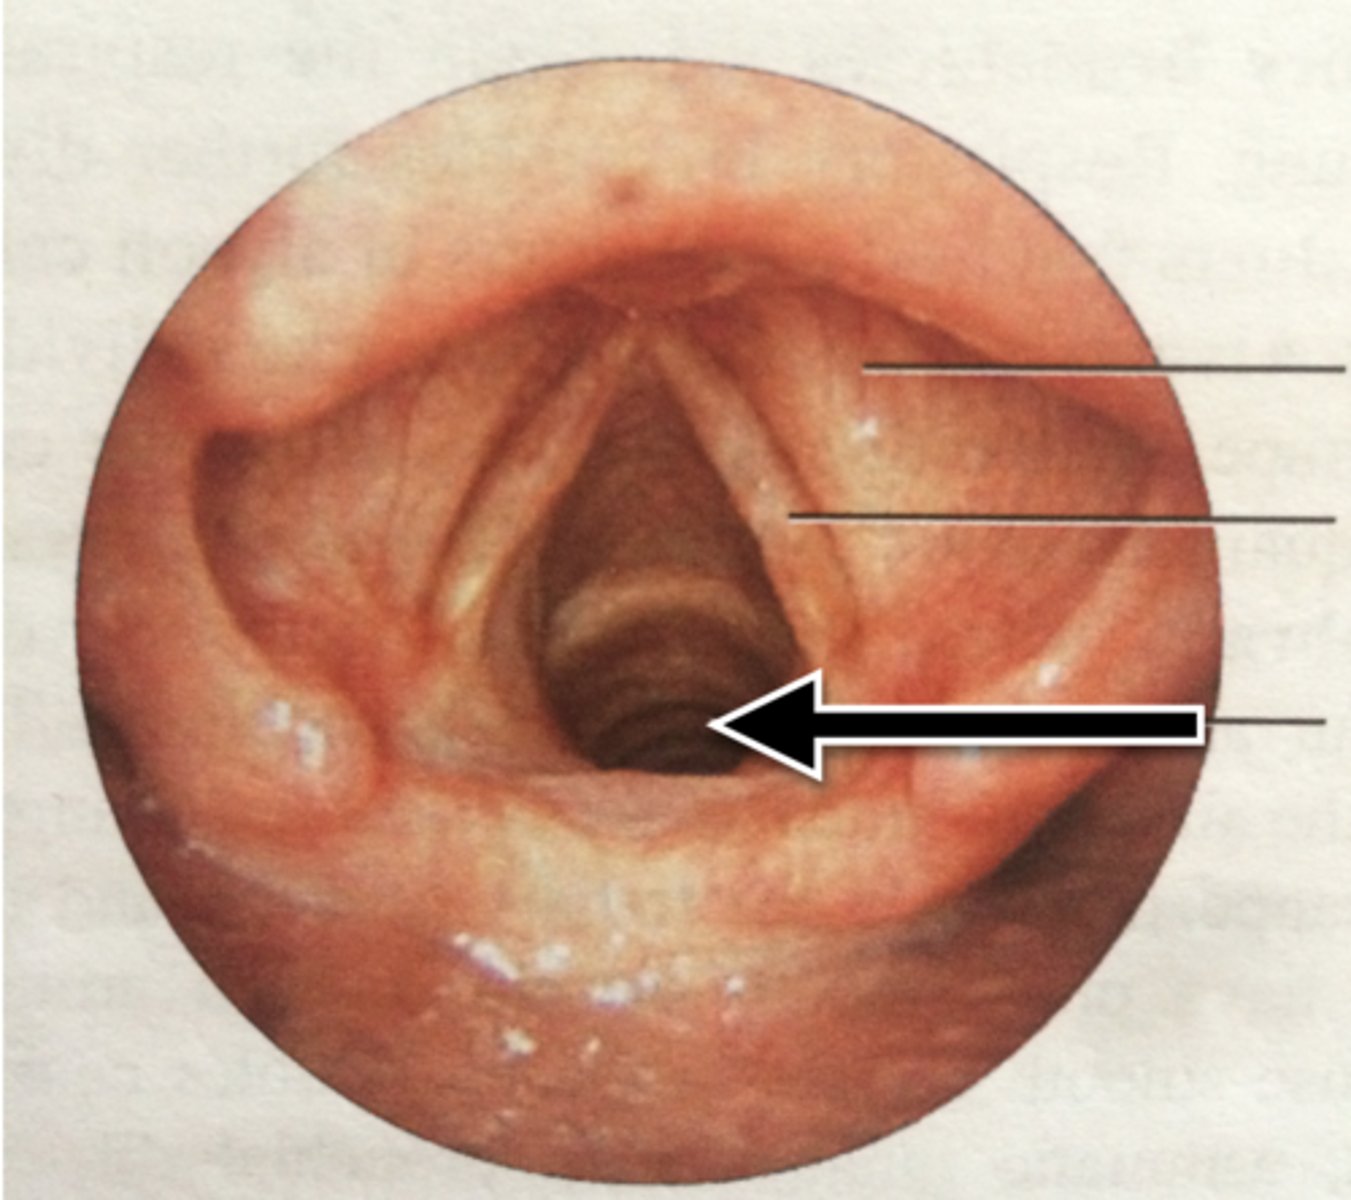

Carina

Glottis